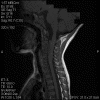

Neuroimaging of the case:

On T1-weighed images, the lesion appeared as a sausage-shaped mass that runs along the long axis of anterior portion of a spinal canal with marked compression of the spinal cord. The mass is well defined from the spinal cord and suggest an intradural, extramedullary location (Panel A). The mass abuts and slightly displaces the left vertebral artery forward. While the intracanalicular portion of the mass is well marginated, the anterolateral, extracanalicular component shows mild infiltration of the musculature. There is slightly heterogeneous enhancement of the mass. Some dural tail enhancement is also present (Panel B). On axial plane, extension of the mass through neuroforamens is well demonstrated (Panel C).